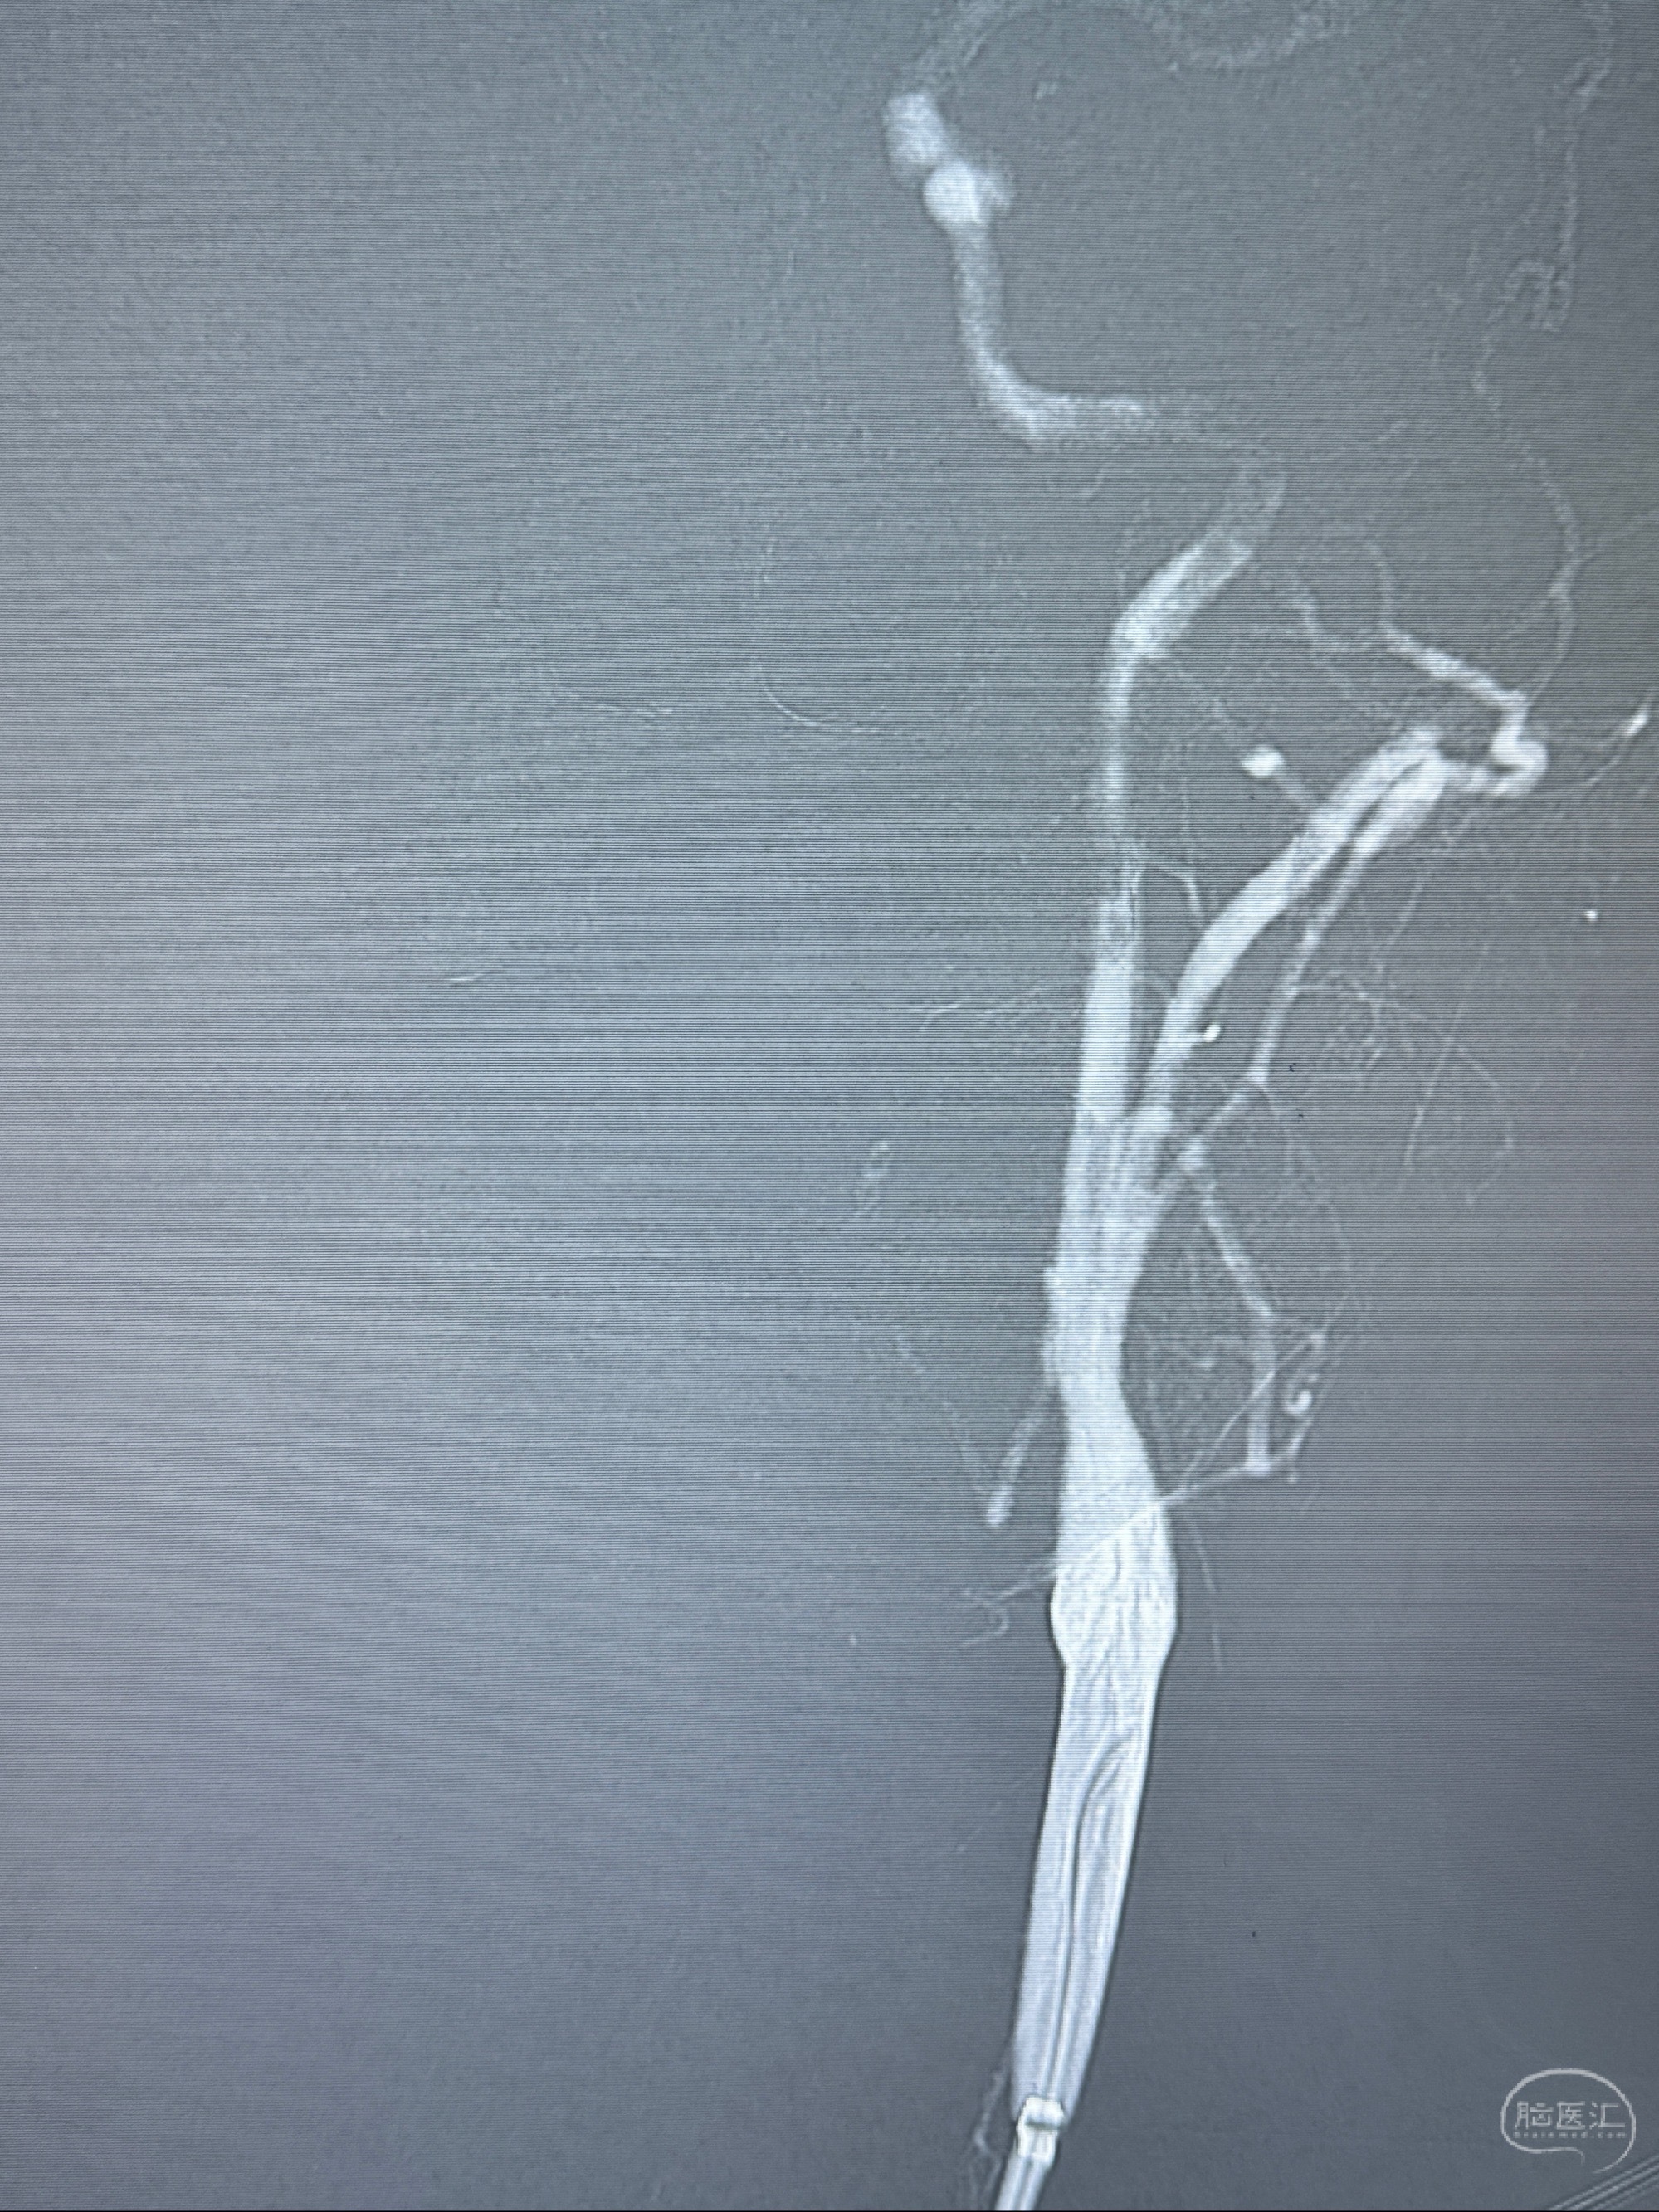

2023-11-01 蓝十字脑科医院 头颅MRI+DWI+MRA:左侧枕叶皮层下小斑片缺血或变性灶,右侧大脑前动脉A1段毛糙,显影淡、纤细,建议完善CTA;

2023-11-03 蓝十字脑科医院 头颅CTA:左侧颈内动脉C6段微小动脉瘤可能(约2mm),右侧大脑前动脉A1段纤细(对侧优势),左侧大脑中动脉提前分叉。

2023-11-13DSA:左侧颈内动脉眼动脉后壁动脉瘤